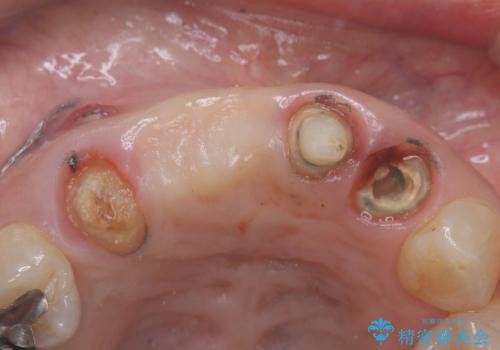

- 歯茎の大きな腫れを主訴に来院された患者様です。前歯5本にはブリッジが装着されていました。レントゲン検査より、右上3番に大きな根尖病巣が認められ、さらに左上1、2番の支台歯にも破折があったため、抜歯を行いました。その後、インプラントを3本埋入し、オールセラミッククラウンのブリッジで補綴しました。

術前のCT画像より、抜歯即時インプラントが可能と判断したため、抜歯と同時にインプラント埋入を行いました。術式にはセミルーナーフラップを用い、唇側の骨吸収を抑える目的でルートメンブレンテクニックを併用しました。